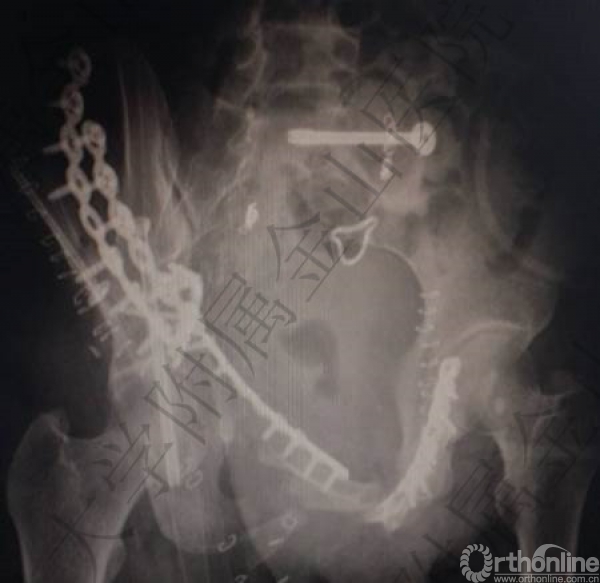

头胸腹CT未见明显实质脏器损伤,骨盆多发骨折:右侧髋臼骨折(双柱)。

骨盆骨折(C2)

2.骨盆多发骨折:右侧髋臼骨折(双柱)骨盆骨折(C2)(失血最主要原因);

骨科:左侧骶髂关节脱位螺钉内固定术(稳定骨盆后环);

手术效果(术后1周)